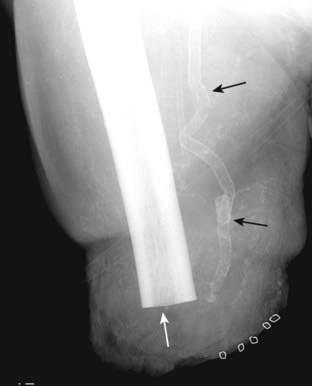

image

Figure 16-4 Calcified arterial wall.

There is linear or tracklike calcification present (solid black arrows), which implies calcification that has occurred in the walls of tubular structures. In the leg, this is calcification in the femoral artery. Such wall calcification occurs in arteries, not veins, and is usually secondary to atherosclerosis, frequently associated with diabetes, or in patients with chronic renal disease. This patient obviously suffered one of the complications of diabetes and has had an above-the-knee amputation (solid white arrow) of a formerly gangrenous leg.